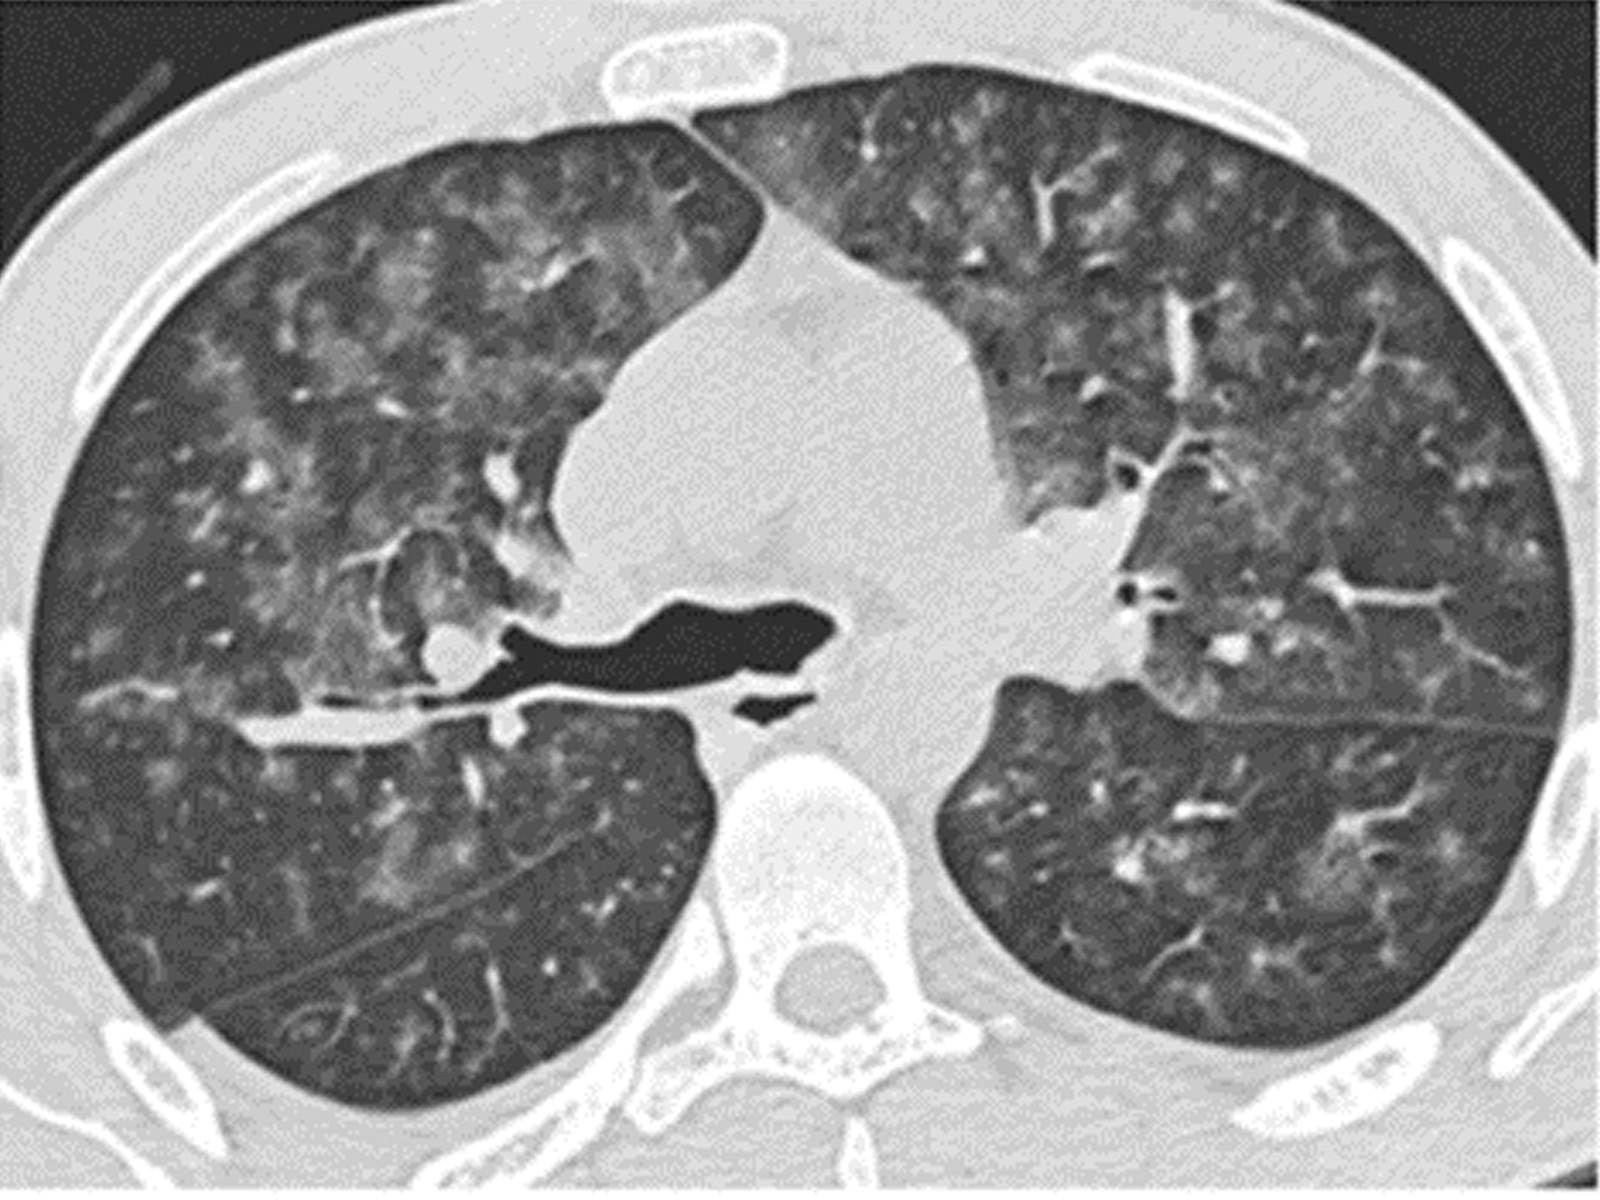

Isolated Diffuse Alveolar Hemorrhage as the Initial Presentation of Microscopic Polyangiitis: A Case Report

Büşra Yıldırım Kafalı, Orkun Eray Terzi, Gülgün Çetintaş Afşar, Seyhan Us Dülger doi: 10.5505/respircase.2026.32656 Pages 32 - 37 |